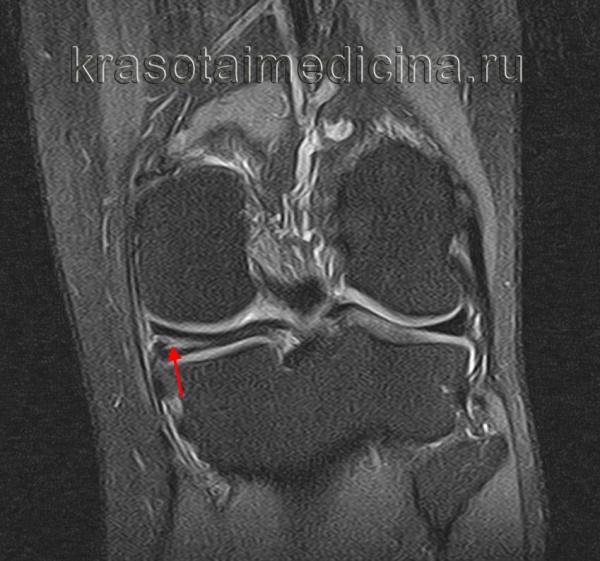

(Слева) МРТ Т2ВИ, режим подавления сигнала от жира, коронарный срез: у пациента 13 лет с болью в колене определяется неполный дискоидный латеральный мениск, который сужается к центру, но покрывает большую часть латеральной поверхности большеберцовой кости. Нормальный латеральный мениск должен покрывать около 50% поверхности большеберцовой кости.

(Справа) MPT PDВИ, коронарный срез: определяется частичный дискоидный медиальный мениск с горизонтальным разрывом. Дискоидные мениски имеют тенденцию к разрыву в большей степени, чем нормальные вследствие увеличения осевой нагрузки и трещины в неабсорбированных областях в центре фиброзного хряща. (Слева) МРТ PDВИ, последующие сагиттальные изображения: определяются признаки дискоидного латерального мениска. При использовании сагиттальных изображений толщиной 3-4 мм обычно не должно визуализироваться более трех полных срезов мениска до отделения переднего и заднего рога; у этого пациента таких срезов пять (самое медиальное изображение отсутствует).

(Справа) МРТ Т2ВИ, режим подавления сигнал от жира, коронарный срез: определяется дискоидный латеральный мениск, содержащий обширный патологический горизонтальный сигнал, указывающий на горизонтальный разрыв. (Слева) МРТ Т2ВИ, режим подавления сигнала от жира, коронарный срез: у пациента 10 лет определяется смещение разорванного дискоидного латерального мениска. Место прикрепления к капсуле разорвано, а более медиальная часть смещена кпереди от межмыщелковой вырезки.

(Справа) МРТ PDВИ, режим подавления сигнала от жира, сагиттальный срез: у этого же пациента определяется крупный латеральный фрагмент мениска в межмыщелковой вырезке с широким пучком повышенного сигнала внутри, характерным для горизонтального разрыва.

2. МРТ при дискоидном мениске коленного сустава:

• Коронарные изображения: утрата нормального сужения, клиновидная форма центрального мениска:

о Частичный дискоидный мениск суживается, но в медиально-латеральном направлении он шире, чем нормальный (>14 мм)

• Сагиттальные изображения: признак продолжающегося вещества мениска в передне-заднем направлении (зависит от толщины среза)